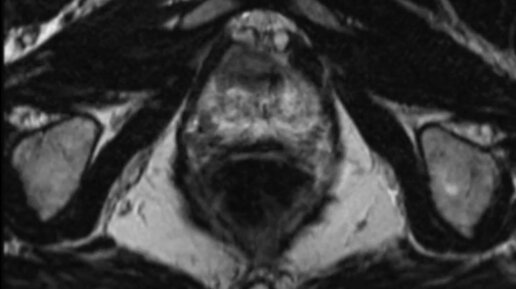

Что покажут снимки МРТ предстательной железы